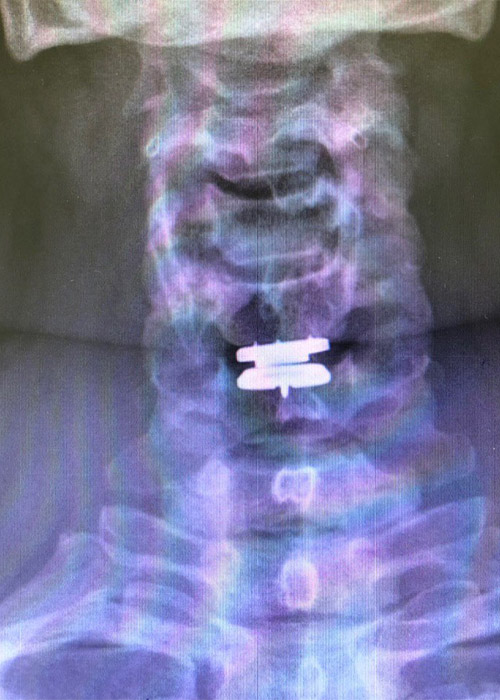

Procedemos a realizar una cirugía donde retiramos la hernia y le colocamos un disco completamente móvil, a través de una incisión de 2 cm a nivel de la piel.

La paciente experimenta una recuperación inmediata post quirúrgica, con inicio de la movilidad del cuello a partir de la media hora de haberse despertado y con el alta médico del hospital en menos de 12 horas.

Cirugia hernia discal postoperatorio

Postoperatorio

La paciente no tiene síntomas de dolor, sin Parestesias en el brazo izquierdo, y nos cuenta que le ha desaparecido la sensación de presión constante que tenía en la zona de la nuca.

La cirugía con resultado satisfactorio y una recuperación inmediata en menos de 24 horas. La paciente puede realizar su vida completamente normal e iniciar la rehabilitación en 4-5 días.